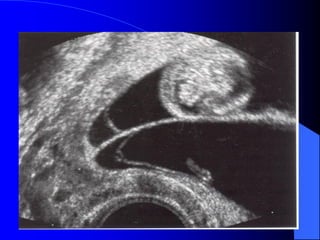

SONG THAI DÍNH I.Ñònh nghóa: - Söï phaân chia khoâng hoaøn toøan cuûa song thai moät hôïp töû. - 70% tröôøng hôïp laø dính ngöïc. II. Taàn suaát : - 1/70 000 treû. - 1/300 song thai moät hôïp töû. Nam < Nöõ .

III. Phoâi hoïc: söïphaân chia khoâng hoøan toøan cuûa dóa phoâi giai ñoïan treã ôû song thai moät hôïp töû (ít nhaát laø 13 ngaøy sau thuï thai) IV. Daáu hieäu sieâu aâm: - Hai ñaàu laø moät daïng ñaëc bieät cuûa song thai dính: moät thaân vaø hai ñaàu. - Ña oái cuõng thöôøng gaëp.

V. Kieåm soaùtlaâm saøng: - Kieåm tra baèng sieâu aâm bao goàm caû sieâu aâm tim. Sieâu aâm kieåm tra ñònh kyø phaùt hieän phuø thai vaø ñaùnh giaù ñoä taêng tröûông. - Tieân löôïng ñöôïc hoäi chaån giöõa baùc só saûn khoa vaø baùc só phaãu nhi. - Thai cheát trong töû cung chieám khoûang 30%.

VI. Chaêm soùcsau sinh: - Ñieàu trò nhöõng bieán chöùng sôùm ñaëc bieät trong tröôøng hôïp treû suy hoâ haáp. Xoa tim coù theå thöïc hieän cho song thai dính ngöïc. - Phaãu thuaät taùch song thai. VII. Tieân löôïng: Tuøy thuoäc vaøo vò trí vaø chieàu daøi cuûa caùc boä phaän bò dính. - Neáu phaãu thuaät tröôùc 3 tuaàn sau sinh thì tæ leä töû vong khoûang 50%, neáu phaãu thuaät töø tuaàn thöù 4 ñeán tuaàn thöù 14 thì tæ leä soáng khoûang 90%.